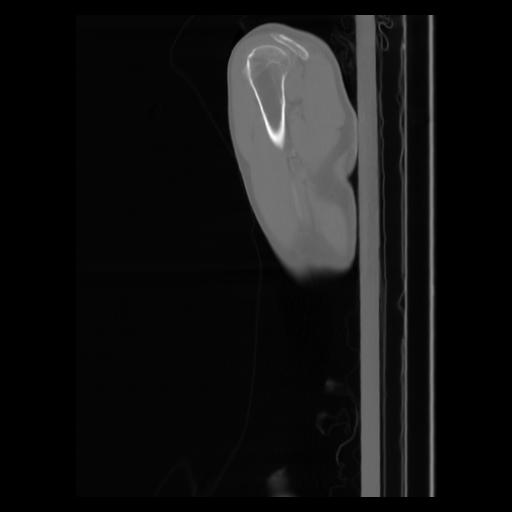

30 CUERPO,CE,Sagittal,3.000,CUERPO,Sagittal,